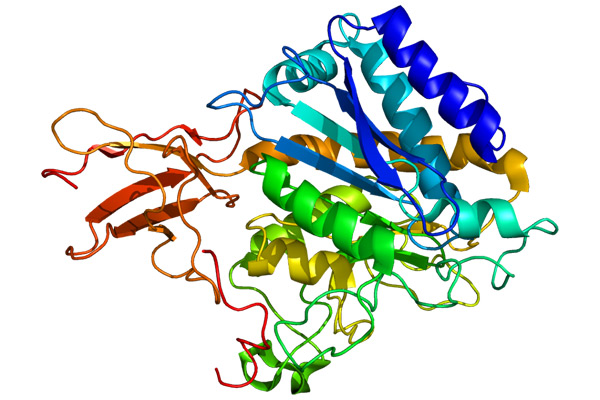

Μετά την αποφοίτησή μου ετάχθην σε ερευνητικό πρόγραμμα του ανωτέρω Πανεπιστημίου υπό την επίβλεψη του καθηγητή Πανεπιστημίου Παθολογικής Ανατομικής Dezso Balazs, ο οποίος επέβλεψε και κατηύθυνε την έρευνά μου. Το σχέδιο έρευνας που κατέθεσα αξιολογήθηκε από τη Feichtinger Foundation με συνακόλουθη απόφαση για χρηματοδότηση του μέχρι ολοκλήρωσης του, απόφαση ιδιαιτέρως τιμητική για μένα.